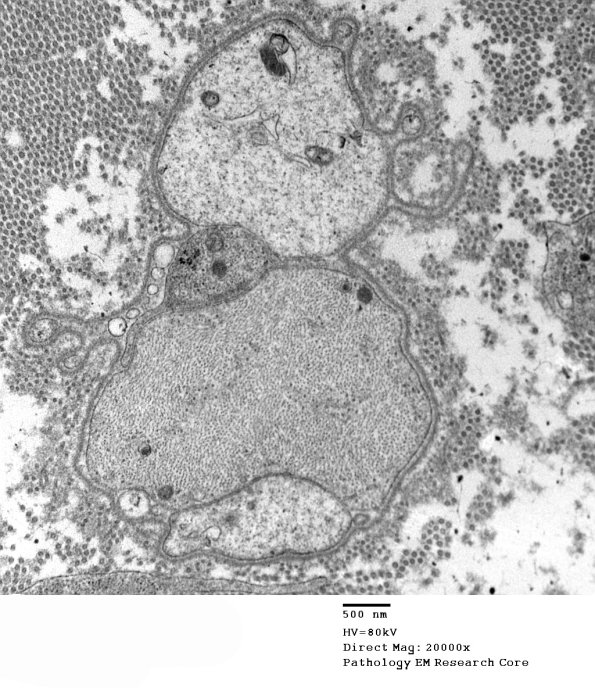

Completely demyelinated axons and scattered associated macrophages. (electron micrographs)